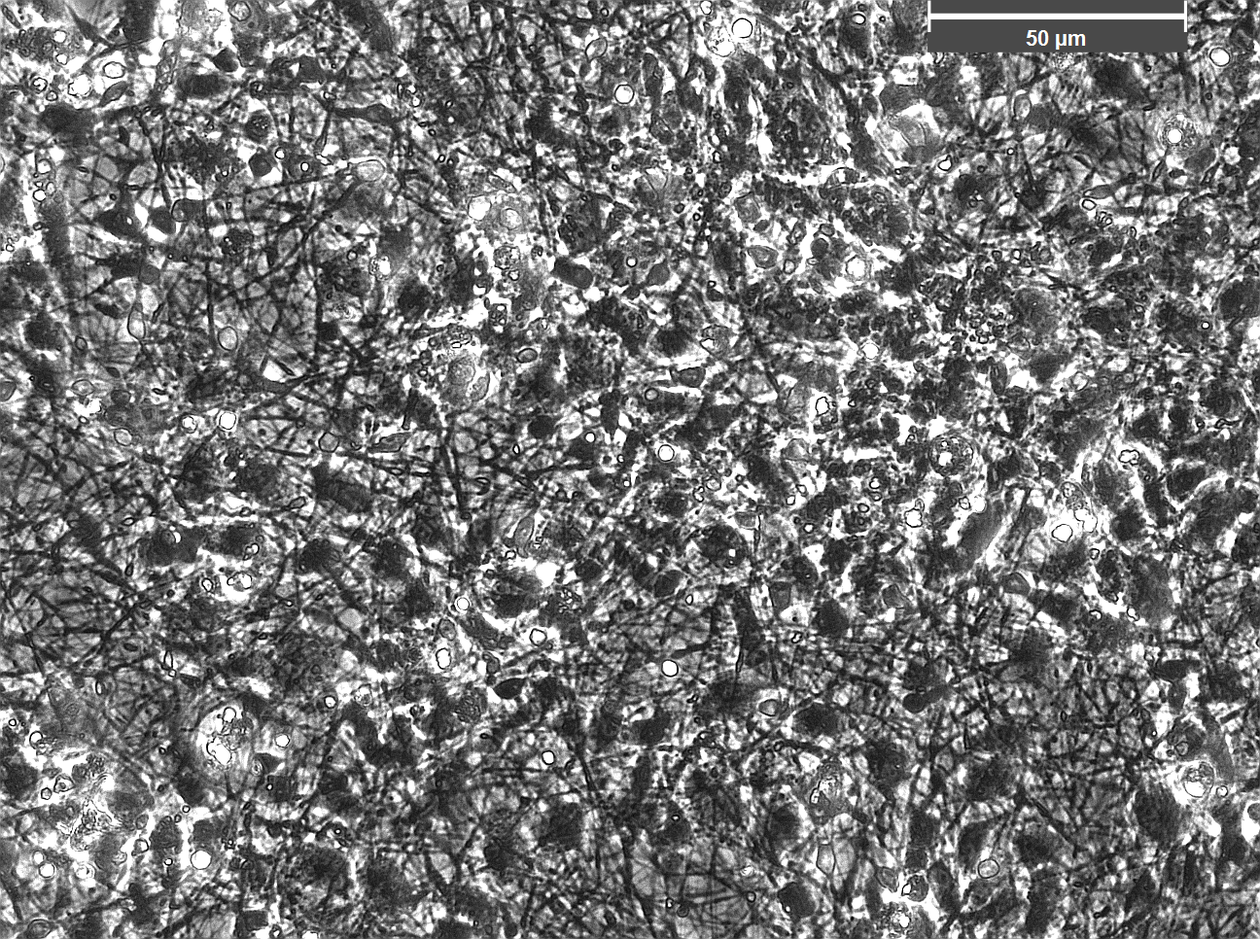

We are using stem-cells transformed from the patient’s own fibroblasts to study the mitochondrial disease caused by POLG mutations. These “induced pluripotent stem cells” (iPSC) offer a unique opportunity to model human disease in a renewable and tissue-specific manner. Thus far we have successfully generated neurones and all glial cell types, cardiomyocytes, and hepatocytes from these iPSCs.

We have established the required competence and facilities for human induced pluripotent stem cell (hiPSC) reprogramming and differentiation, enabling investigation of neuronal cells from patients and healthy controls. Validated iPSCs are differentiated to neural stem cells (NSCs) and regionalized neuronal subtypes, as well as astrocytes/ glial populations. A postdoctoral fellow in our group, Yu Hong, has developed brain organoids and will be using these both to investigate disease mechanisms and to test treatments.

- 2D: neural stem cells, DA neurons, motor neurons, generic neurons, astrocytes, oligodendrocytes and cardiomyocytes.